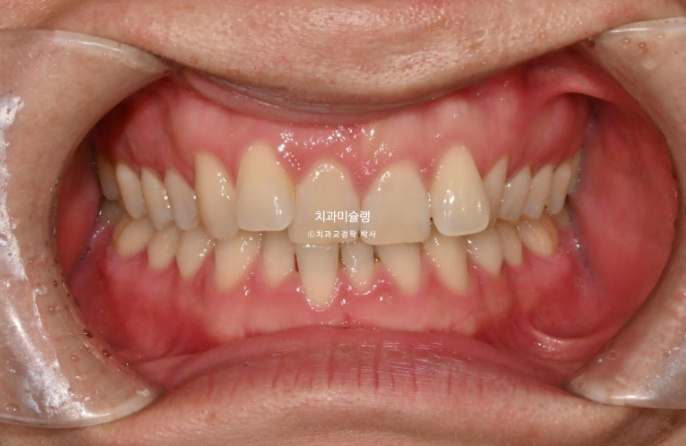

25.04

중심선이 맞지 않고 잇몸라인이 들쑥날쑥 합니다.

잇몸라인이 들쑥날쑥한 이유는 덧니 때문입니다.

어금니 교합관계는 좌우가 다른 상태라 위아래 중심선이 맞지 않습니다.

이렇게 측절치만 튀어나가있고 중절치는 옥니처럼 안으로 들어간 상태를 2급 2류 부정교합이라고 합니다.